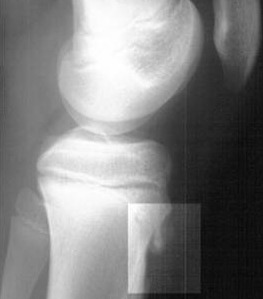

X-ray 검사를 합니다. 성장단계에 따라 크기는 다르지만 경골조면 즉 무릎의 바로 아래에 국한된 골단핵 변화, 유리골편이라는 것이 보여집니다. MRI검사를 하면 연골부를 덮고 있는 슬개건이 두꺼워져 있거나 주변 염증성 변화를 확인할 수 있습니다. 초음파로도 돌출된 뼈와 인대 비후도 볼 수 있습니다.